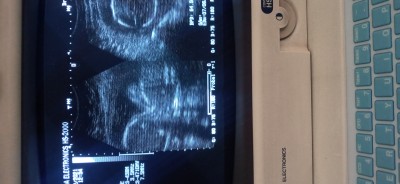

Sizce nedir yanılma payı olabir mı

Döktor erkege Benziyor dedi sizce de öyle mı

Gebelik haftası

25

Doktor erkek dediyse erkektir 25 hafta olmus aetik herseyi oluşmuş